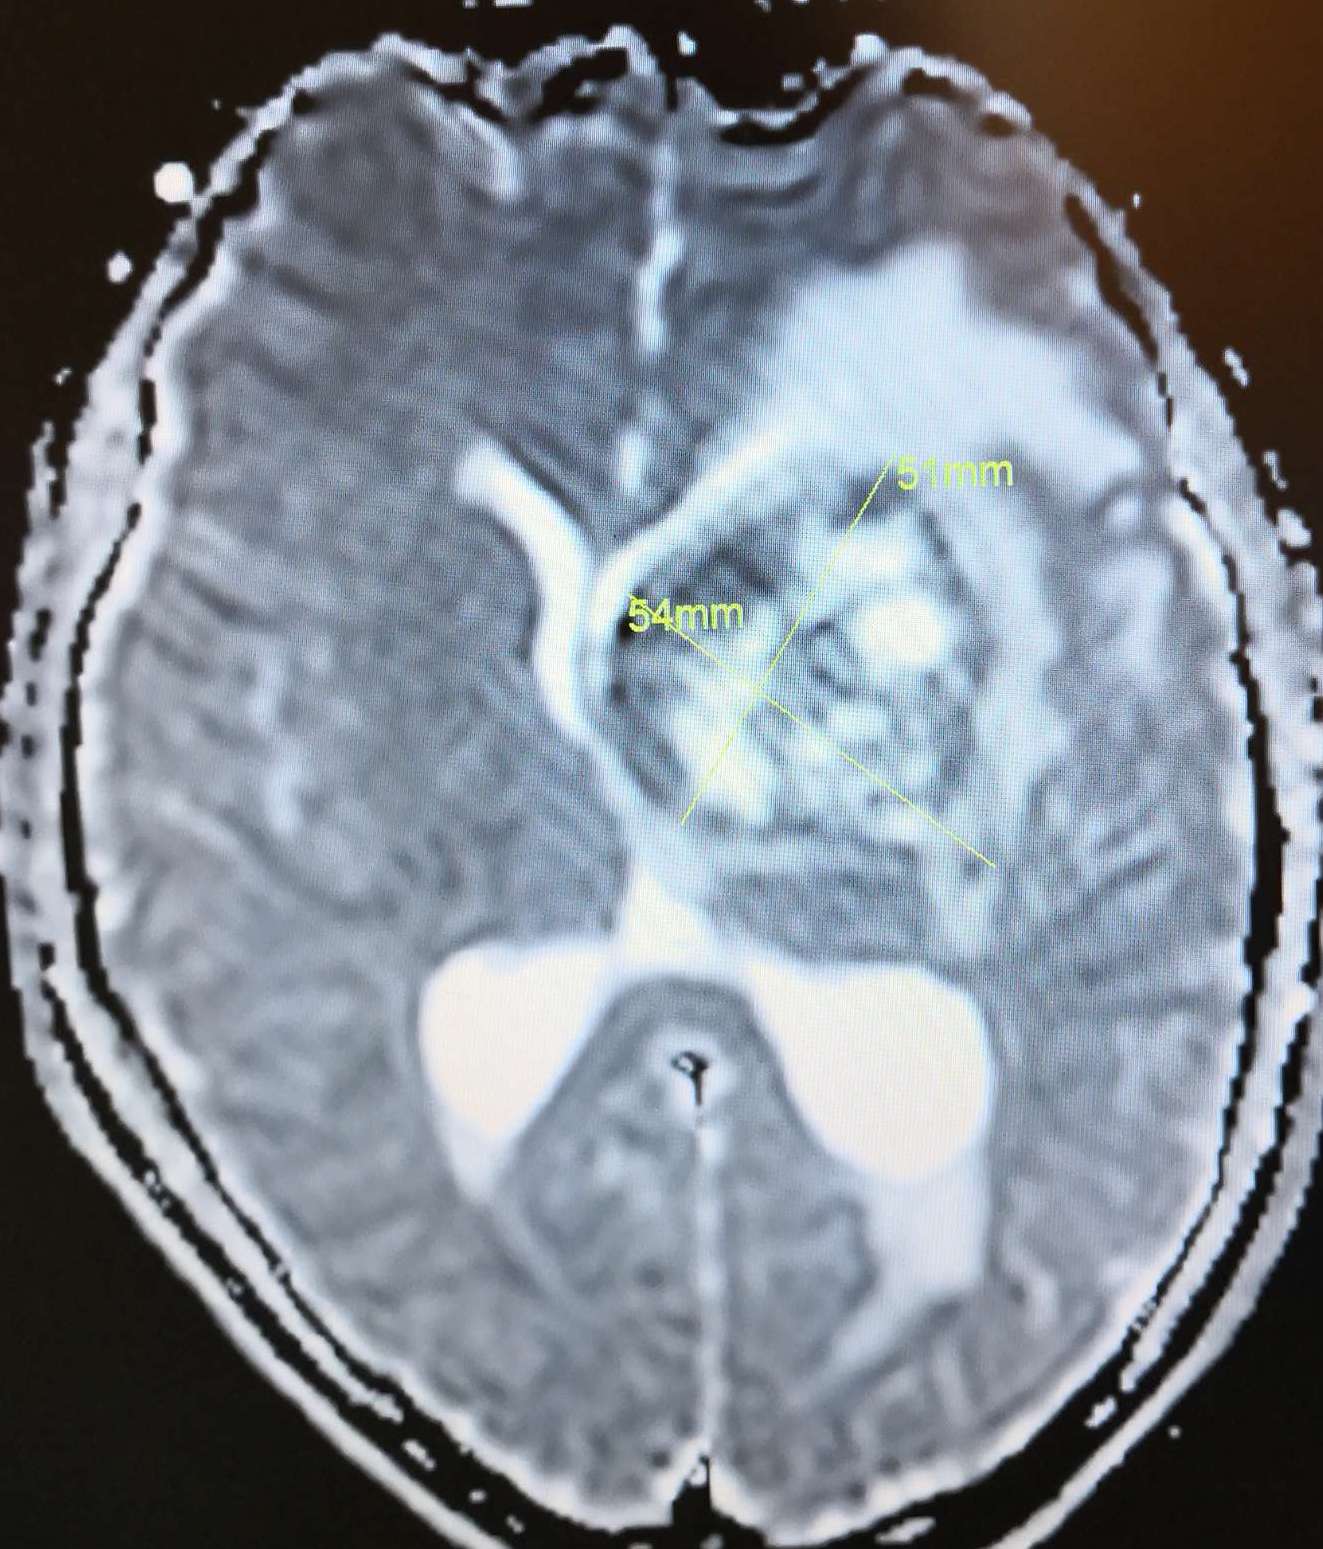

术前头颅MRI ADC显示:左侧基底节巨大占位病灶(51*54mm),呈高、低值,脑室受压,中线移位明显。